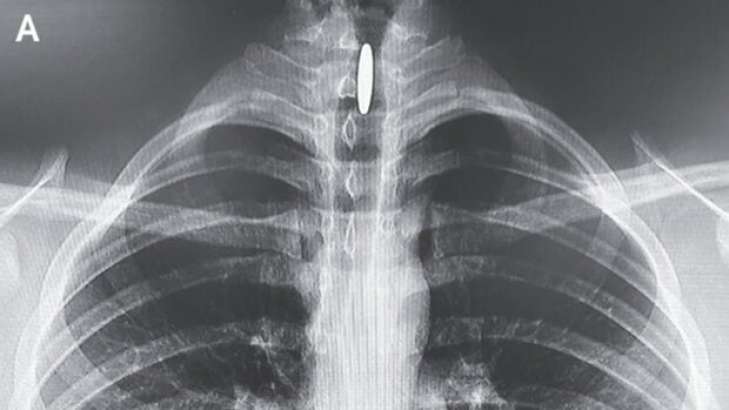

У 14-летнего подростка, которого доставили в отделение неотложной помощи с непонятной хрипотой голоса и затрудненным глотанием, при обследовании обнаружили посторонний округлый предмет.

Как пишет издание The New England Journal of Medicine, этот объект находился в вертикальном положении в подголосовой щели. Прямо, как монетка в монетоприемнике игрового автомата.

Предмет, как впоследствии выяснилось, действительно был 25-центовой монетой, которая застряла между голосовыми связками и трахеей. Парень объяснил, что шесть часов назад случайно проглотил монетку, вернее думал, что проглотил.